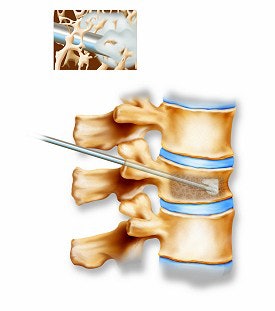

Above, the acrylic bone cement flows into the vertebra, filling the trabecular spaces within the bone. Inset shows a magnified view of the interior of the vertebra with the cement filling in the spaces. Below, the restored vertebra with the hardened cement, stabilizing the vertebral structure and relieving pain. Inset shows magnified view of the interior of the restored vertebra.